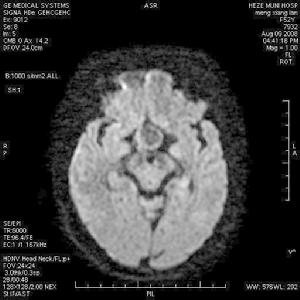

蝶鞍擴大可見於下丘腦或垂體腫瘤。微腺瘤蝶鞍無擴大但可有局限性破壞,CT或MRI有助進一步診斷。